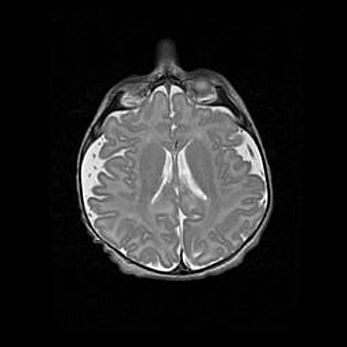

Наружная гидроцефалия с возможной атрофией височных областей.

Возраст: 28 дней

Вес: 3670 г

Пол: мужской

Окружность головы: 38 см

Срок гестации: 40 недель

Гидроцефалия головного мозга у новорожденных – это заболевание, которое характеризуется скоплением избыточного количества спинномозговой жидкости в желудочковой системе головного мозга в результате затруднения её перемещения от места выработки к месту поглощения в кровеносную систему или вследствие нарушения абсорбции. При открытой наружной форме гидроцефалии у новорожденных расширяются и переполняются субарахноидные пространства.

При нормотензивных  формах,  которые,  как  правило,  являются  следствием  перенесенных ишемических  повреждений  паренхимы  мозга,  возможно  сочетание микроцефалии  с нормотензивной гидроцефалией. В основе данных изменений лежит атрофия больших полушарий с преимущественной  локализацией  в  лобно-височных  областях.